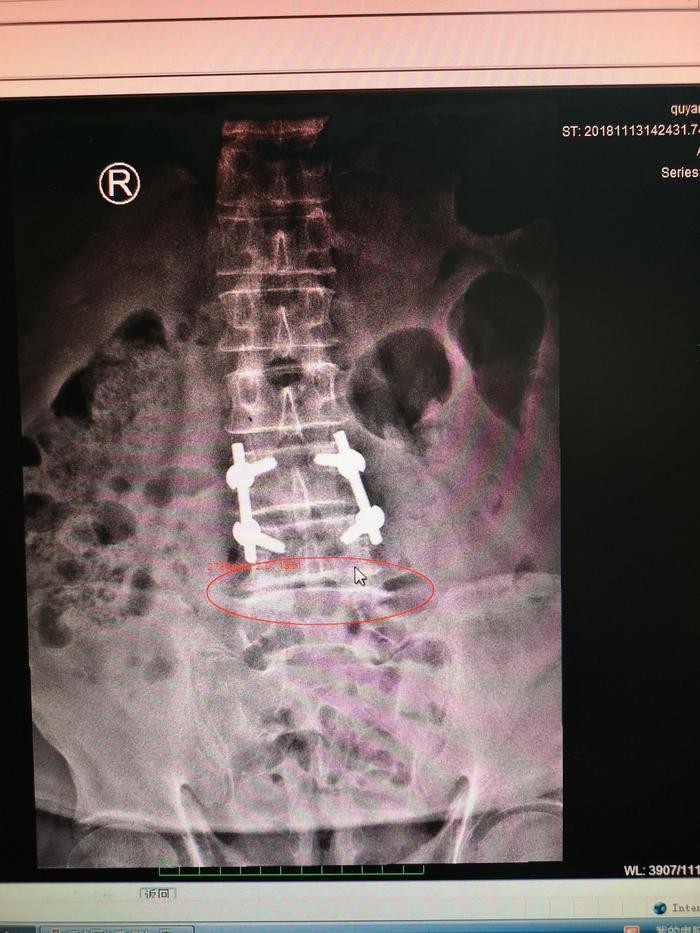

下面的是一位腰间盘手术后进行内固定治疗,术后1年的患者的X光片子。

我们可以对照一下手术前和手术之后我标记的部位的关节的改变

开x光片上,我们可以看到治疗前腰4-5椎体间关节是病变不明显的,那么治疗之后椎体间出现了间隙变窄,硬化,增生加重,而脊柱侧弯骨盆旋移都没有得到纠正。术后不到1年再次出现腰痛,不能背伸,也不能侧弯。

分析运动力学原因是因为第三第四,腰椎被固定之后,这两节腰椎的力量通过杠杆的作用都传达到第4、5腰椎上导致这一节段的腰椎负荷加重,出现不平衡损伤进一步加重,此类患者跟我一再强调,他手术做好了,腰间盘突出就好了,事实上并非如此,因为可以引起腰痛的疾病非常多,所以也不是做掉椎间盘手术腰就一定会好了。